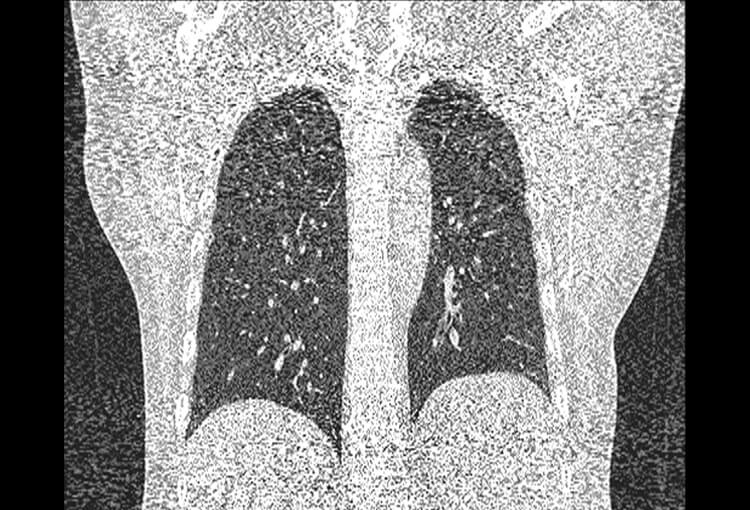

Before and After Denoising

120 kV / 30 mAs / 1mm

Before FBP (Noise 150) VS After ClariCT.AI (Noise 49) 67% Denoising